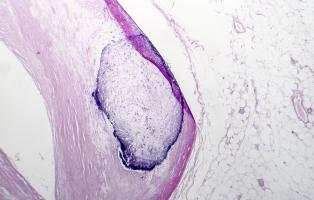

ATHÉROSCLÉROSE : Des nanoplastiques à côté de la plaque

ATHÉROSCLÉROSE : Et si le cholestérol n'était pas le seul lipide impliqué ?

ATHÉROSCLÉROSE : Réaliser les promesses des sphingolipides

ATHÉROSCLÉROSE : La plaque plus tardive mais plus nocive chez les femmes ménopausées

Actualité publiée le 16/06/2023ATHÉROSCLÉROSE : Prévenir l'obstruction des artères en boostant l’autophagie

ATHÉROSCLÉROSE : Le nutraceutique qui dissout les blocages athéroclérotiques

ATHÉROSCLÉROSE : Mais comment stabiliser la plaque ?

Actualité publiée le 19/07/2022ATHÉROSCLÉROSE : Le laser qui vaporise la plaque